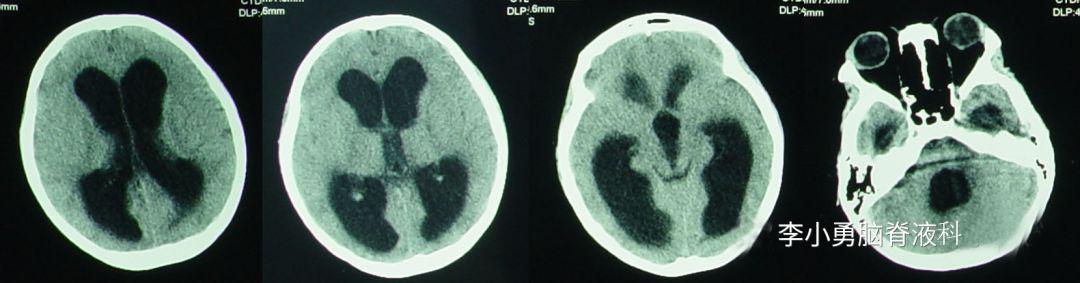

在2010年5月23日(发病后17天)转入小儿神经内科后,腰穿脑脊液检查的结果提示白细胞数显著增多,达到>2000的严重程度,进一步查头颅核磁(图-1)后,诊断为“化脓性脑膜炎”,抗感染治疗(万古霉素,美罗培南等)治疗18天。

图-1:2010年5月23日头颅核磁